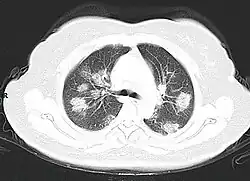

A CT scan of a person with COVID-19 shows lesions (bright regions) in the lungs

Chest CT scans may be helpful to diagnose COVID‑19 in individuals with a high clinical suspicion of infection but are not recommended for routine screening.[175][187] Bilateral multilobar ground-glass opacities with a peripheral, asymmetric, and posterior distribution are common in early infection.[175][188] Subpleural dominance, crazy paving (lobular septal thickening with variable alveolar filling), and consolidation may appear as the disease progresses.[175][189] Characteristic imaging features on chest radiographs and computed tomography (CT) of people who are symptomatic include asymmetric peripheral ground-glass opacities without pleural effusions.[190]

Many groups have created COVID‑19 datasets that include imagery such as the Italian Radiological Society which has compiled an international online database of imaging findings for confirmed cases.[191] Due to overlap with other infections such as adenovirus, imaging without confirmation by rRT-PCR is of limited specificity in identifying COVID‑19.[190] A large study in China compared chest CT results to PCR and demonstrated that though imaging is less specific for the infection, it is faster and more sensitive.[174]